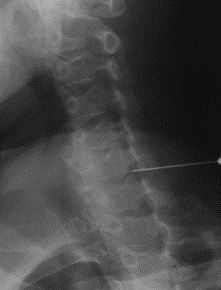

第二日 颈椎神经根阻滞明确责任节段

细针穿刺,定位!医生注射了一点麻药, “疼痛离开就缓解了许多!”